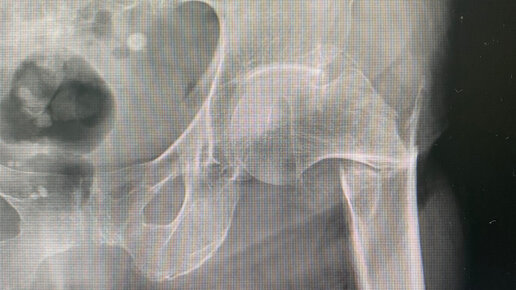

Чрезвертельный перелом бедренной кости - тяжелый перелом, требующий правильного подхода

Есть два вида переломов, которые зачастую затрагиваю людей преклонного возраста - перелом шейки бедра и чрезвертельный перелом бедренной кости. Чрезвертельный перелом - это перелом бедренной кости, который проходит между большим и малым вертелом бедренной кости. Обычно это более благоприятный перелом по сравнению с переломом шейки бедра, так как при переломе шейки бедра лечение координально отличается и у людей старше 60 лет чаще всего требует эндопротезирования тазобедренного сустава. А при при...